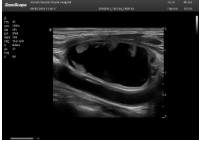

肥厚性心肌病-心尖四腔

探頭面是平面,接觸面小,近場視野最小,遠(yuǎn)場視野大,成像視野呈扇形,適用于心臟。

心臟探頭通常按應(yīng)用人群劃分為成人、兒童、新生兒三類:(1)成人心臟位置最深、搏動(dòng)速度慢;(2)新生兒心臟位置較淺、搏動(dòng)速度最快;(3)兒童心臟的情況介于新生兒與成人之間。